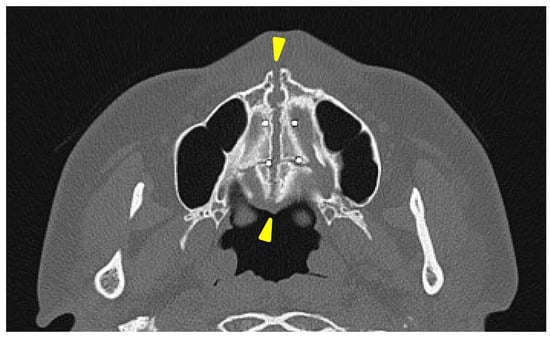

A head CT was performed on the same day. The axial slices revealed a 4 mm wide separation of the midpalatal suture (Figure 3). A fracture of the left maxilla was also observed. The line of this fracture extended from the orbital floor and the anterior surface of the maxilla (Figure 4), starting at the medial edge of the orbital rim, passing through the entire wall of the infraorbital foramen (Figure 5a,b), and reaching the maxilla’s alveolar process.

Figure 4. Three-dimensional computed tomography image of facial bones. A fracture line extending from the infraorbital rim to the infraorbital foramen (Circle mark) and a separation of the midpalatal suture (yellow triangle marks) were observed.